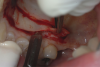

Fig 9. Preoperative view of a patient with moderate recession requiring root coverage and increased thickness of the alveolar housing.

Figure 9

A patient presented with moderate recession requiring root coverage and increased thickness of the alveolar housing (Figure 9). A series of parallel incisions was completed using instruments made specifically for microsurgery; these incisions were performed utilizing high magnification (ie, 5.5 magnification via loupes). The distance between the incisions was roughly the amount of root coverage necessary on the adjacent teeth (Figure 10).25

The isthmus of tissue between the parallel incisions was removed. A split-thickness flap was elevated leaving connective tissue on the bone and providing access for root preparation.